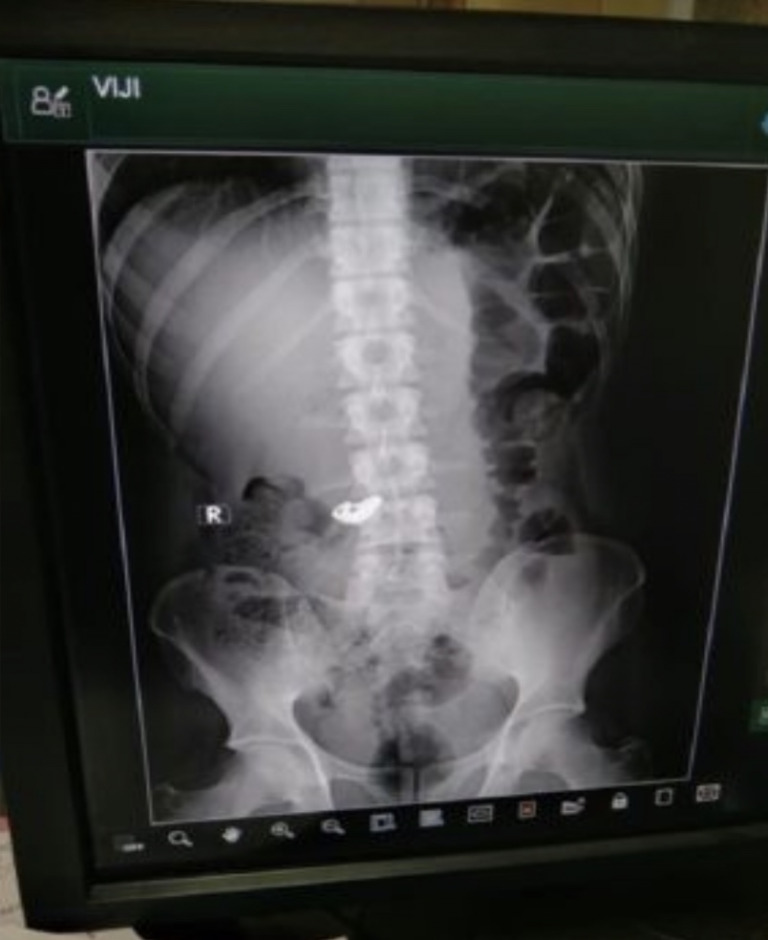

Lelaki itu kemudiannya dibawa ke balai polis sebelum dihantar ke hospital bagi merawat kecederaannya akibat dipukul dan hasil imbasan sinar X mendapati Thali menelan rantai emas tersebut.

Namun, lelaki itu tidak mengakui menelan rantau emas berkenaan dan memaklumkan objek dalam imbasan itu merupakan tulang yang ditelannya sebelum kejadian.